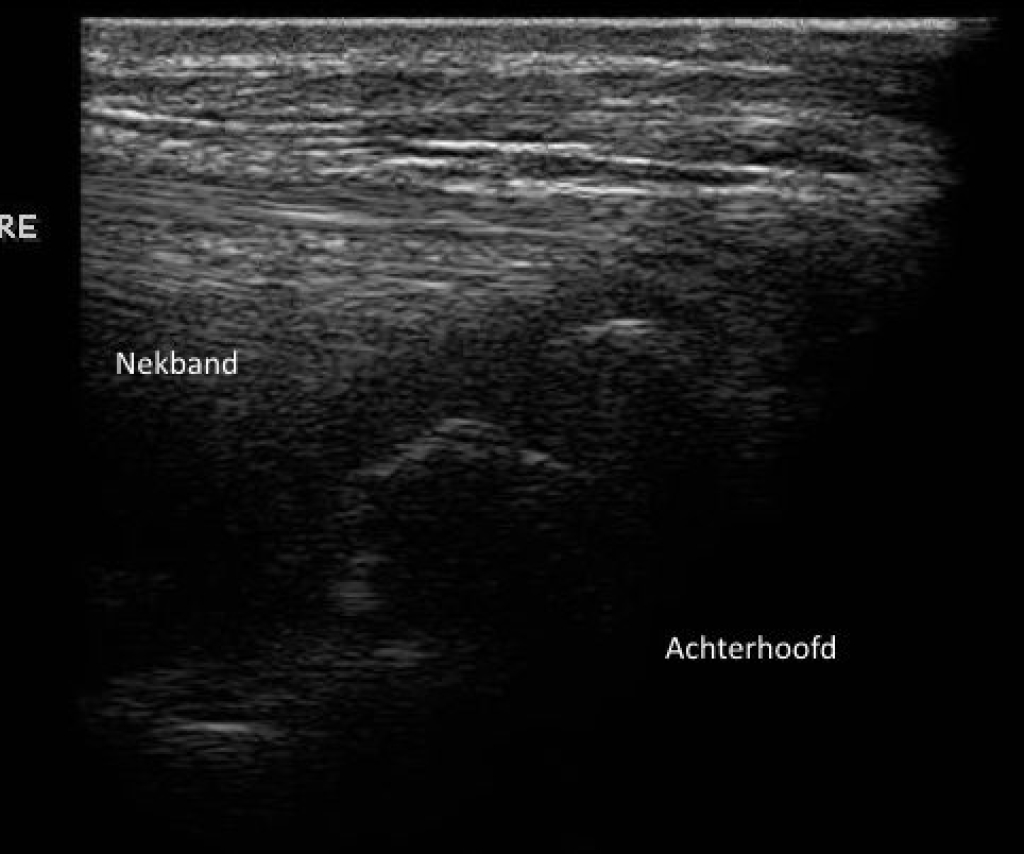

Echobeeld en röntgenfoto van het achterhoofd

Foto: Echobeeld en röntgenfoto van het achterhoofd

Het afvoelen van het gebied van de aanhechting van het ligamentum nuchae leidt niet altijd tot een duidelijke pijnreactie. Om de diagnose te kunnen stellen is het daarom nodig om het gebied in beeld te brengen met röntgenfoto’s en een echo. Omdat veranderingen die we waarnemen met röntgen en echo niet altijd in relatie staan tot klinische problemen kunnen de beelden nooit los gezien worden van de klachten bij het paard. Belangrijk hierbij is de mate van botbeschadiging, botactiviteit en of ook de aanhechting van de semispinalispees betrokken is. Zo zien we veel paarden met een onregelmatige botbelijning van het achterhoofd, zonder dat deze klachten hoeven te hebben.

Rechts: Echografie van de nekband van hetzelfde paard als de röntgenfoto

Echografie van de nekband van hetzelfde paard als de röntgenfoto